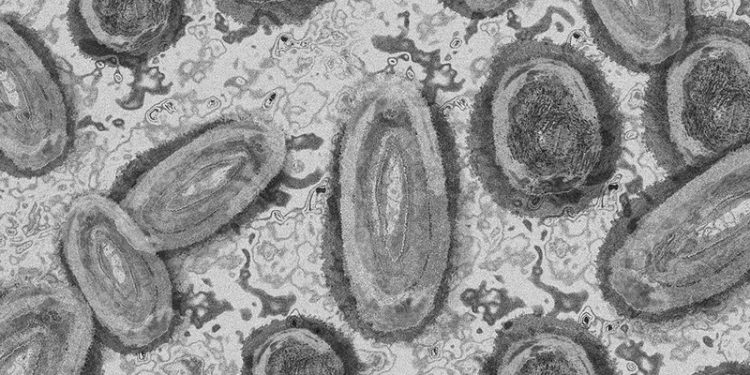

La Dirección General de Salud Pública está siguiendo de manera rigurosa el protocolo establecido desde el comienzo de la expansión de esta enfermedad. Los síntomas habituales de la enfermedad son erupciones en manos y cara y otras zonas del cuerpo, que en ocasiones van acompañadas de fiebre, dolor de cabeza y cuerpo e inflamación en los ganglios.

La transmisión del mpox es por contacto directo con lesiones cutáneas, fluidos corporales de una persona infectada o con objetos contaminados utilizados por personas infectadas, como ropa de cama o ropa. También se han documentado otras vías de contagio, como a través de gotas respiratorias grandes durante el contacto cara a cara directo y prologado o la transmisión de madre a hijo, si bien es entre parejas sexuales, debido al contacto íntimo, el modo más probable de infección.